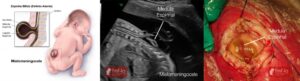

Mielomeningocele

Definição: A mielomeningocele é o tipo mais grave de espinha bífida, onde a medula espinhal e as meninges protrudem através da abertura na coluna vertebral, formando um saco visível nas costas.

Sintomas: Este tipo de espinha bífida resulta em danos neurológicos significativos, levando a fraqueza muscular, paralisia, perda de sensibilidade, problemas de controle intestinal e vesical, e outras complicações.

Diagnóstico: Geralmente diagnosticada durante a gravidez ou ao nascimento. Exames de ultrassom e testes de alfa-fetoproteína (AFP) são comumente usados para detectar a meningocele.